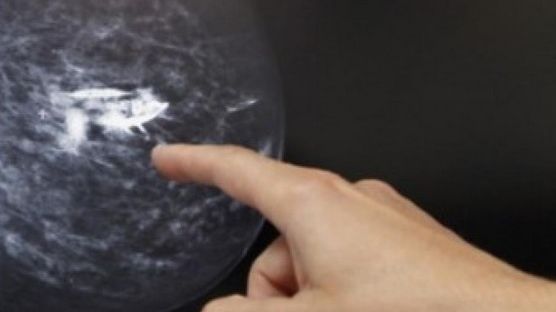

Ce NU spun medicii despre mamografii. Tot ce trebuie să ştii despre screeningul pentru cancer

Extrem de neplacut atat pentru femei, cat si pentru barbati, screeningul pentru cancerul mamar sau de prostata reprezinta o procedura care deja face parte din viata fiecarui om, pentru a se asigura ca este sanatos. In cazul in care rezultatele nu sunt cele asteptate, cancerul poate fi tratat mult mai usor intrucat a fost descoperit devreme.

Cu siguranta predispozitia genetica joaca un rol important in aparitia cancerului, insa nu reprezinta o garantie a faptului ca se va intampla asa. Daca aveti cazuri in familie cu cancer mamar de exemplu, este recomandat sa mergeti anual la o mamografie, astfel incat sa reusiti sa preveniti aparitia bolii. Inca nu se stie cu exactitate daca screeningul depisteaza cancerul sau, mai rau, determina aparitia lui.